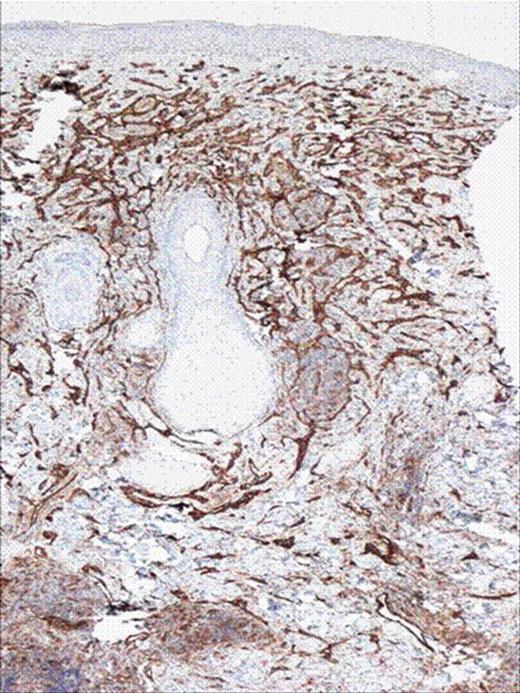

A 50 year old male with past medical history of diabetes, hypertension was diagnosed with angiosarcoma localized to the face (Figure 1 & Figure 2). The patient had baseline mild coagulopathy before start of chemotherapy most likely from the angiosarcoma. He received the first cycle of paclitaxel and bevacizumab but required hospitalization four days later for chest pain and acute coronary syndrome was ruled out. He then developed febrile neutropenia with an ANC of 0.0 and progressive pancytopenia. On day 9 of chemotherapy, the patient had a platelet count of 12 K/μ L with hemoglobin of 6.1gm/dl, hematocrit of 18% and WBC count of 3 k/μ l. The peripheral smear revealed many schistocytes, in addition elevated LDH 1112U/L, with an indirect bilirubin of 2.62 mg/dl, total bilirubin of 3.80mg/dl, and a haptoglobin of less than 10. His coagulopathy progressed with a PT of 17.3, PTT 65.3, fibrinogen degradation products (FDP) which were less than 10 on day 6 post chemo, were more than 40 on day 8 and his D-Dimers were 13.5 mg/l(Figure 5). ADAMTS13 level was drawn and though his creatinine and mental status remained normal, plasmapharesis was initiated with the presumptive diagnosis of thrombotic thrombocytopenic purpura (TTP).

H& E stain of punch biopsy of the lesion from the cheek showing infilterating vascular tumor.